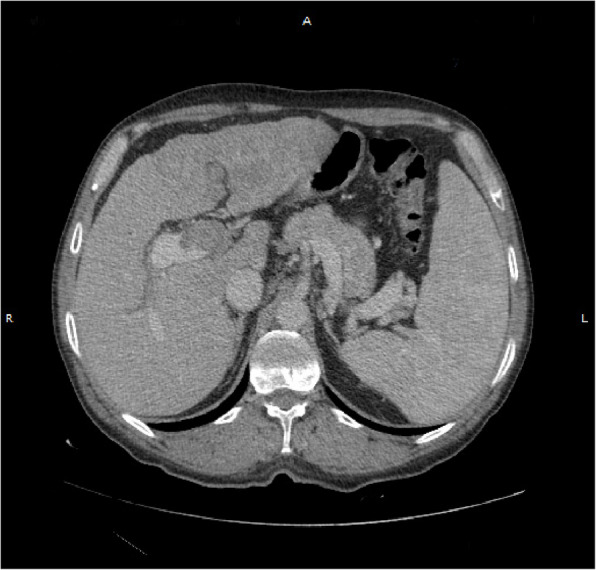

Case description: We present the clinical case of a 57-year-old male patient with a documented history of hepatitis C virus infection but without prior evidence of active hepatocellular carcinoma. Over the course of several months, he developed a non-tender, progressively enlarging mass located in the occipital region of the skull. A computed tomography (CT) scan identified a lytic lesion with intracranial compression, although no midline shift was noted. Histopathological examination confirmed the lesion as metastatic HCC, further supported by immunohistochemical markers Hepatari- 1 and Cytokeratin- 19. Subsequent diagnostic procedures revealed hepatic lesions, including a positron emission tomography (PET)-CT scan. Further examination through CT imaging of the abdomen with contrast highlighted a well-defined focal lesion in hepatic segment 4a, measuring 4.3 × 4.3 cm, predominantly enhancing with HCC characteristics. The skull lesion was surgically removed en bloc, and the patient underwent adjunct radiotherapy and systemic therapy, with palliative therapy till his death in May 2024. To better understand and manage this atypical presentation, we conducted a review for the discussion of clinical manifestations, imaging findings, pathological features, and patient outcomes associated with HCC skull metastases.